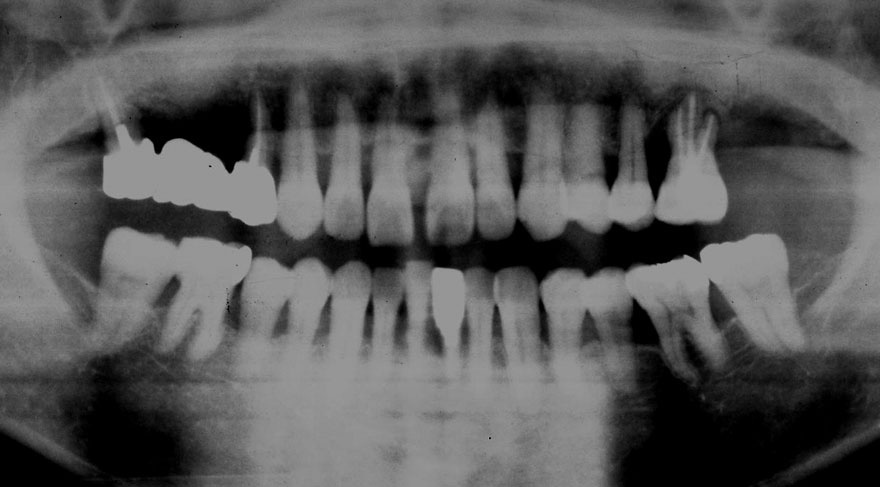

初診時 40歳 女性 平均歯槽骨喪失量:5.24mm

20年後 60歳

平均歯槽骨喪失量:5.79mm

21年間喪失量:-0.55mm

年間喪失速度:-0.027mm

(ケア頻度:1.23ヵ月ごと)